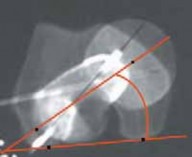

3. A number of imaging techniques have been described to estimate femoral anteversion, including plain radiography,11 fluoroscopy, CT,4,14,23 ultrasonography,25 and MRI10 (

FIG 3

).

FIG 3 • CT method of estimating femoral anteversion involves overlapping images of three slices: the femoral head, the femoral neck at the base, and the distal femur through the femoral condyles.